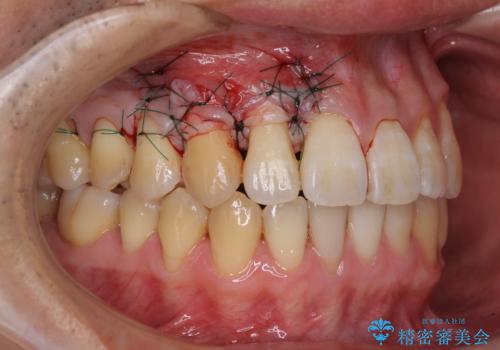

八重歯の歯根が見えている点も気になっているので、矯正歯科治療後に歯肉移植による根面被覆を行うこととしました。

矯正治療により元々気になっていた八重歯と、反対咬合が改善された歯の2本に対して根面被覆を行い、審美面の改善も達成しました。

- 外科手術のため、術後に痛みや腫れ、違和感を伴います

- 歯周組織再生治療は患者様の状態によって術後の経過が異なります(見た目が改善しない場合もあります)

- 歯周組織再生治療は自費診療(保険適用外)となります